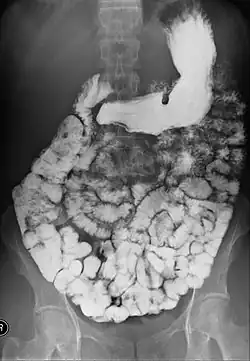

- Barium follow-through examinations are used to study the small intestine.[2]

Small bowel follow-through

Indications to do this procedure are: unexplained chronic abdominal pain with weight loss, unexplained diarrhea, anemia which is caused by gastrointestinal bleeding or dependent on blood transfusion where the cause cannot be explained despite OGDS or colonoscopy investigations, partial obstruction of bowel/small bowel adhesive obstruction suspected, and unexplained malabsorption of nutrients.[13] For barium follow-through examinations, a 6-hour period of fasting is observed prior to the study.[10]

Barium is administered orally, sometimes mixed with diatrizoic acid (gastrografin) to reduce transit time in the bowel. Intravenous metoclopramide is sometimes also added to the mixture to enhance gastric emptying.[17] 600 ml of 0.5% methylcellulose can be given orally, after barium meal is given, to improve the images of small bowel follow-through by reducing the time taken for barium to pass through the small intestines, and increase the transparency of the contrast-filled small bowels.[18] Other methods to reduce transit time are to add ice cold normal saline after the administration of barium saline mixture[19] or to give a dry meal.[20]

X-ray images are then taken in a supine position at intervals of 20–30 minutes. Real-time fluoroscopy is used to assess bowel motility. The radiologist may press or palpate the abdomen during images to separate intestinal loops. The total time necessary for the test depends on the speed of bowel motility or transit time and may vary between 1 and 3 hours.[17]

- Barium follow-through examinations are the most commonly used imaging technique in assessing patients with Crohn's disease, although CT and magnetic resonance imaging are widely accepted as being superior.[1] However Barium examinations remain superior in the depiction of mucosal abnormalities.[24] The features of Crohn's disease are well described by barium follow-through examinations, appearing as a typical "cobblestone pattern", but no information is obtained regarding extraluminal disease.[28] Radiographic imaging in Crohn's disease provides clinicians with objective evaluations of small bowel regions that are not accessible to standard endoscopic techniques.[29] Because of its length and complex loops, the small intestine is the most difficult part of the gastrointestinal tract to evaluate. Most endoscopic techniques are limited to the examination of proximal or distal segments, hence Barium follow-through remains in most centres the test of choice for the investigation of abdominal pain, diarrhoea and in particular diseases manifesting mucosal abnormalities such as coeliac and Crohn's disease.[26]